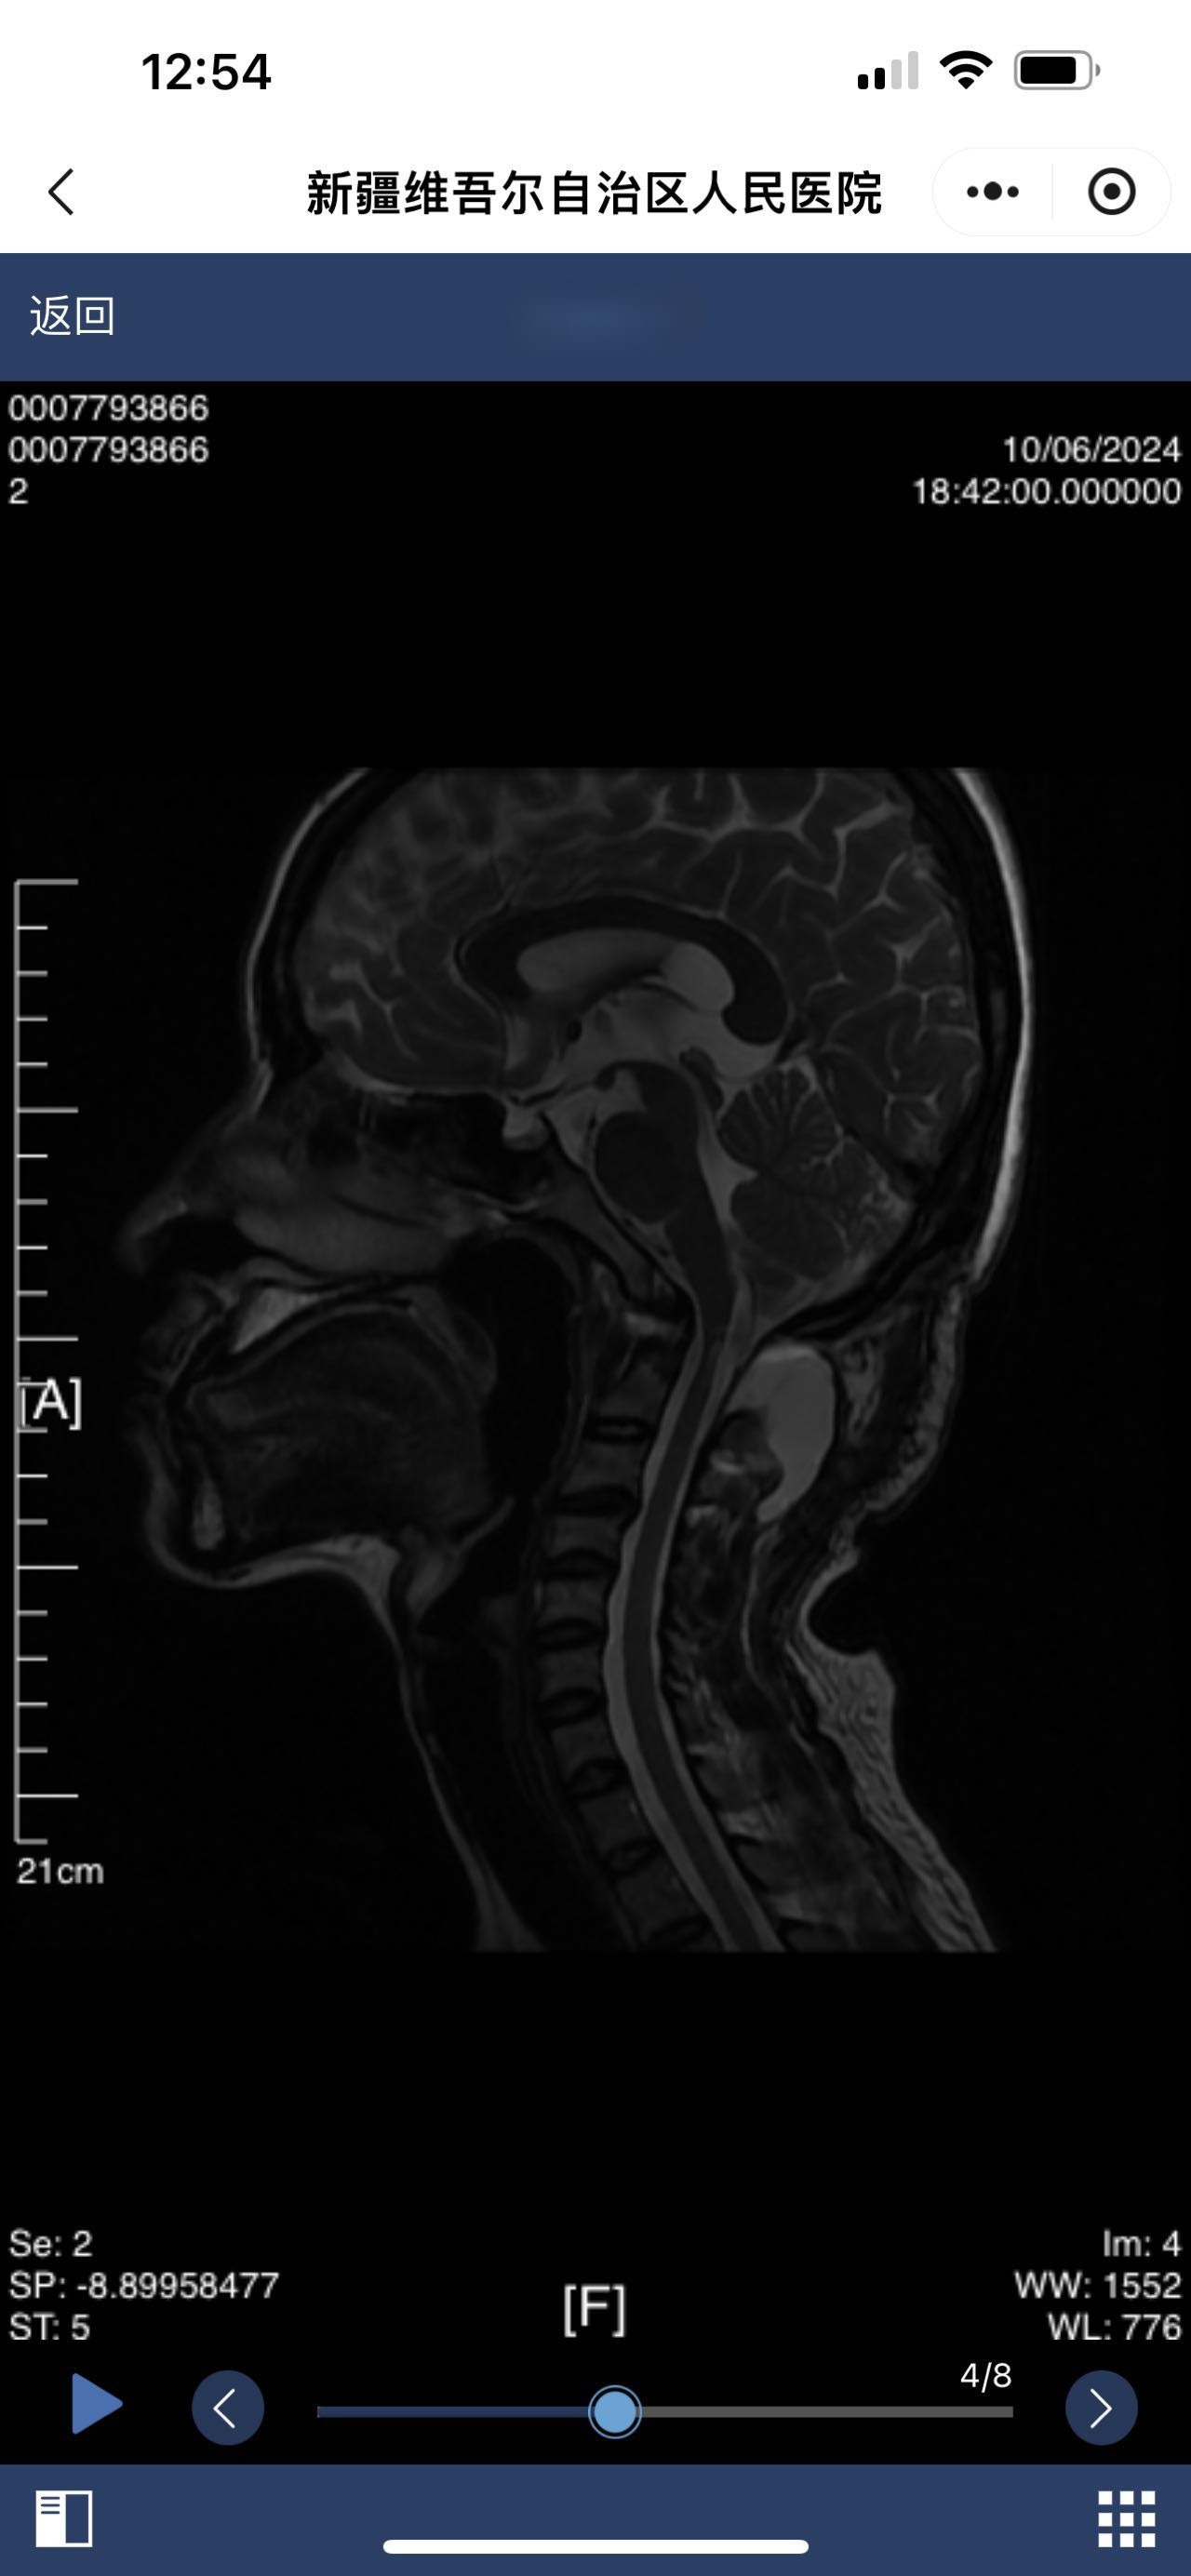

• 术后状况:术后颈后有积液

• 术后影像: